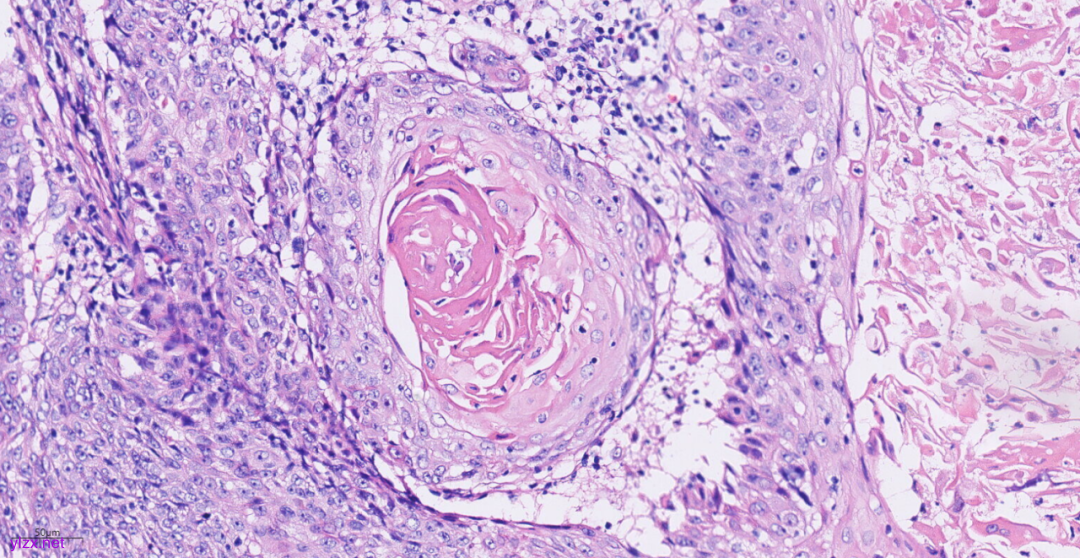

3.2镜下观(图3-图9):

低倍镜下可见卵巢肿物呈囊,中倍镜下,囊壁见分化成熟的多胚层成分,成熟型囊性畸胎瘤区域可见皮肤(正常鳞状上皮及其表明角化物)及其附属器成分(皮脂腺、汗腺及毛囊),局部囊壁表面可见由正常鳞状上皮-原位癌-鳞状细胞癌逐渐过渡;在鳞状细胞癌区域,囊壁增生的纤维结缔组织中可见肿瘤细胞呈巢状向下浸润性生长,也向囊腔内乳头状生长,局部癌巢中央可见角化珠及坏死;高倍镜下,鳞癌成分肿瘤细胞大小不等,细胞排列紊乱,细胞中-重度异型,核大深染,略呈空泡状,核仁明显,核分裂象易见,伴角化珠形成。

图7 高倍镜下,癌巢中央可见角化珠。

图8 高倍镜下,高分化鳞癌细胞之间可见细胞间桥。

图9 高倍镜下,中分化鳞癌细胞呈空泡状,核仁明显,核分裂象易见。